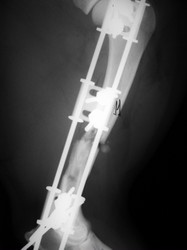

Fijación Externa

Fijación externa en IVOT

PRÁCTICAS CURSO DE FIJACIÓN EXTERNA PERFECCIONAMIENTO.

Húmero.